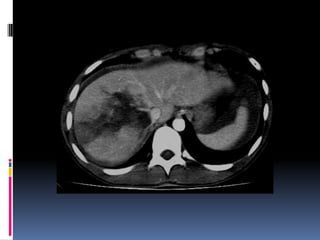

INJURIA HEPÁTICA

Grados de severidad

RadioGraphics 2009; 29:2033–2053

INJURIA HEPÁTICA Grados de severidad RadioGraphics 2009; 29:2033–2053